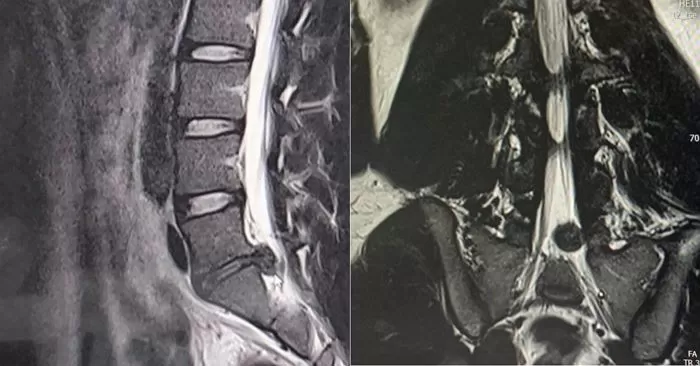

이 사실을 중대장에게 알려 휴가를 쓰게 된 A씨는 민간 병원에서 MRI 촬영 후 허리 디스크 수술을 받게 됐다. 병원장에게 '군 생활 어떻게 했냐'는 질문을 받을 정도로 상태는 심각했다고 한다.

A씨의 허리 상태 / Facebook '육군훈련소 대신 전해드립니다'